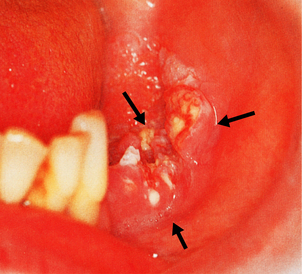

Intra-oral cancers most frequently affect the tongue and commonly develop in areas of leukoplakia (Fig. 15.2); many oral carcinomas are associated with leukoplakia when diagnosed. The predisposing causes are therefore the same as those for leukoplakia but with the possibility that human papillomavirus (HPV) could also be implicated. ‘High-risk’ HPVs (mainly type 16 or 18) are more frequently associated with oral squamous carcinoma than low-risk HPVs. Like lip cancers, oral cancers are usually squamous carcinomas. Initially they are painless and can remain undetected, especially if situated on the posterior third of the tongue, until fixation and swelling interfere with swallowing and speech. Late presentation with nodal metastases and direct spread to vital structures explains the much poorer prognosis of cancer of the tongue compared to that of cancer of the lip.

image

Fig. 15.2 Oral cancer. Ulcerated squamous cell carcinoma (arrowed) arising from buccal mucosa.

(Courtesy of Mr P McAndrew, Rotherham.)